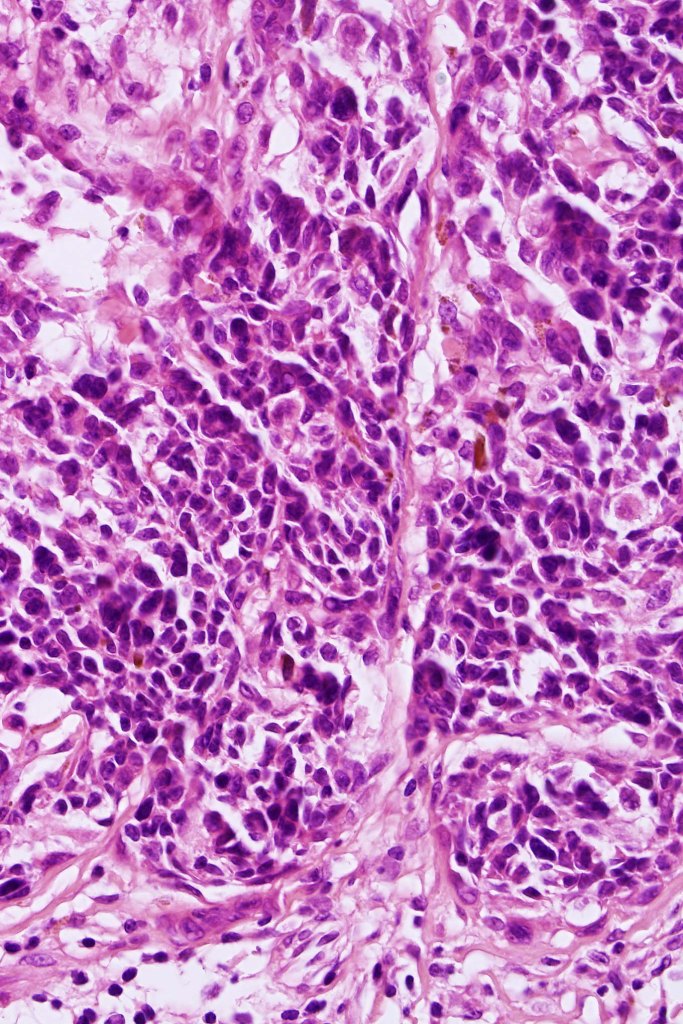

Combined congenital & blue nevus (same case as the clinical photographs coursty of Dr. Antonina Kalmykova